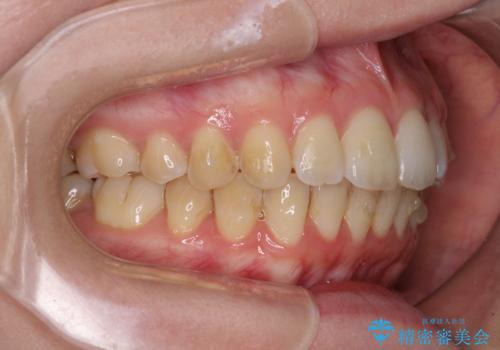

前歯のデコボコを解消 インビザラインによる矯正治療

- 上下前歯のデコボコと深い咬み合わせを気にして来院された患者様です。

インビザラインによる上下歯列の拡大と、IPR(歯と歯の間を削る)にるスペースの獲得により、前歯のデコボコを改善することとしました。

上の前歯をもう少し整えたかったのですが、患者様の治療を早く終了させたいという希望により、細かい叢生を残しての終了となりました。